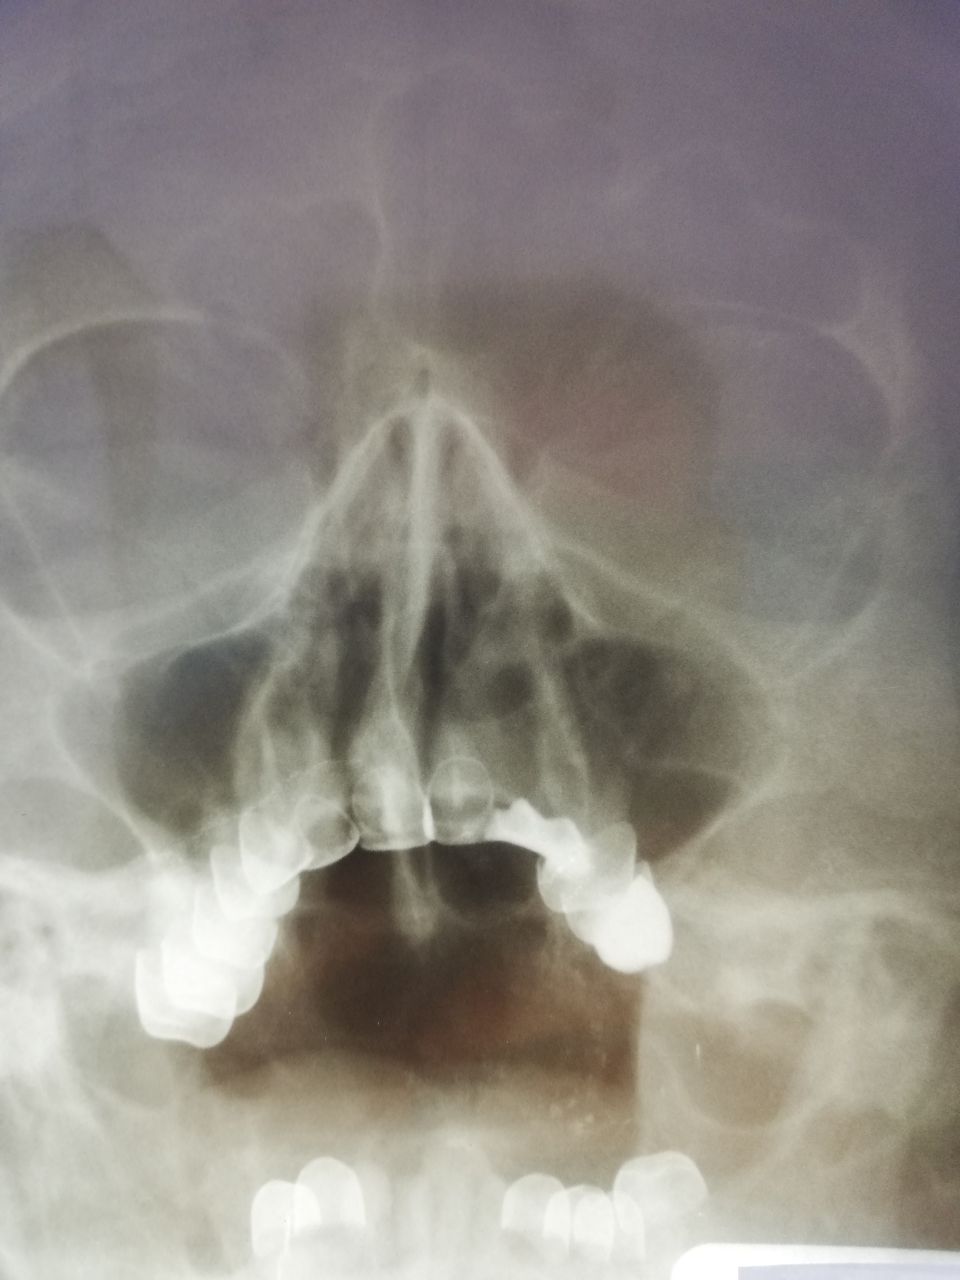

Добрый день, уважаемые коллеги! Женщина, 67 лет, идет на операцию. Есть ли справа синусит? Уплотнение локальное, не по всей стенке, и по форме не очень похоже на отек. Или тут норма и отпустить ее на операцию?

источник

Норма.